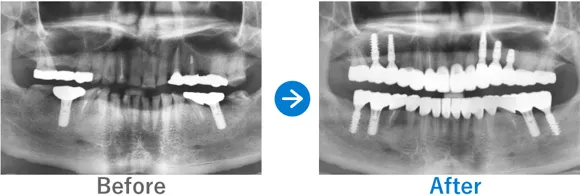

ほとんどの歯が残存していないケース

Case1

歯が1本もない状態からインプラント治療で噛める幸せを取り戻された方

歯が1本もない状態、10年以上前から上下総義歯(総入れ歯)

上顎ALLON6、下顎ALLON4、

リオペ上顎追加埋入ザイゴマインプラント2本

9,823,000円(上顎6,248,000円、下顎3,575,000円/内訳:上顎オールオン6(ノーベルザイゴマインプラント2本・ストローマンインプラント4本)、下顎オールオン4(ストローマンインプラント4本)3Dモデルガイド*、仮歯、セデーション、ボツリヌストキシン注射、3D模型、保証10年)

来院の背景

10年以上前から上下義歯(総入れ歯)だが、義歯が痛くて、食事に困っている。他院にて仮義歯を作ってもらっていたが担当医が辞めたこともあり、インプラントを検討。ネットで探して退院。痛みなく食事がしたい。

治療結果

上下ALLON4、右上5、左上3、リオペザイゴマインプラント2本追加順調の経過、治療終了、メンテナンス来院。インプラントで噛めるようになり、喜んでいただいた。しっかりセルフケアを頑張っておられます。お顔の表情も明るくなられて、気持ちも前向きに過ごされています。